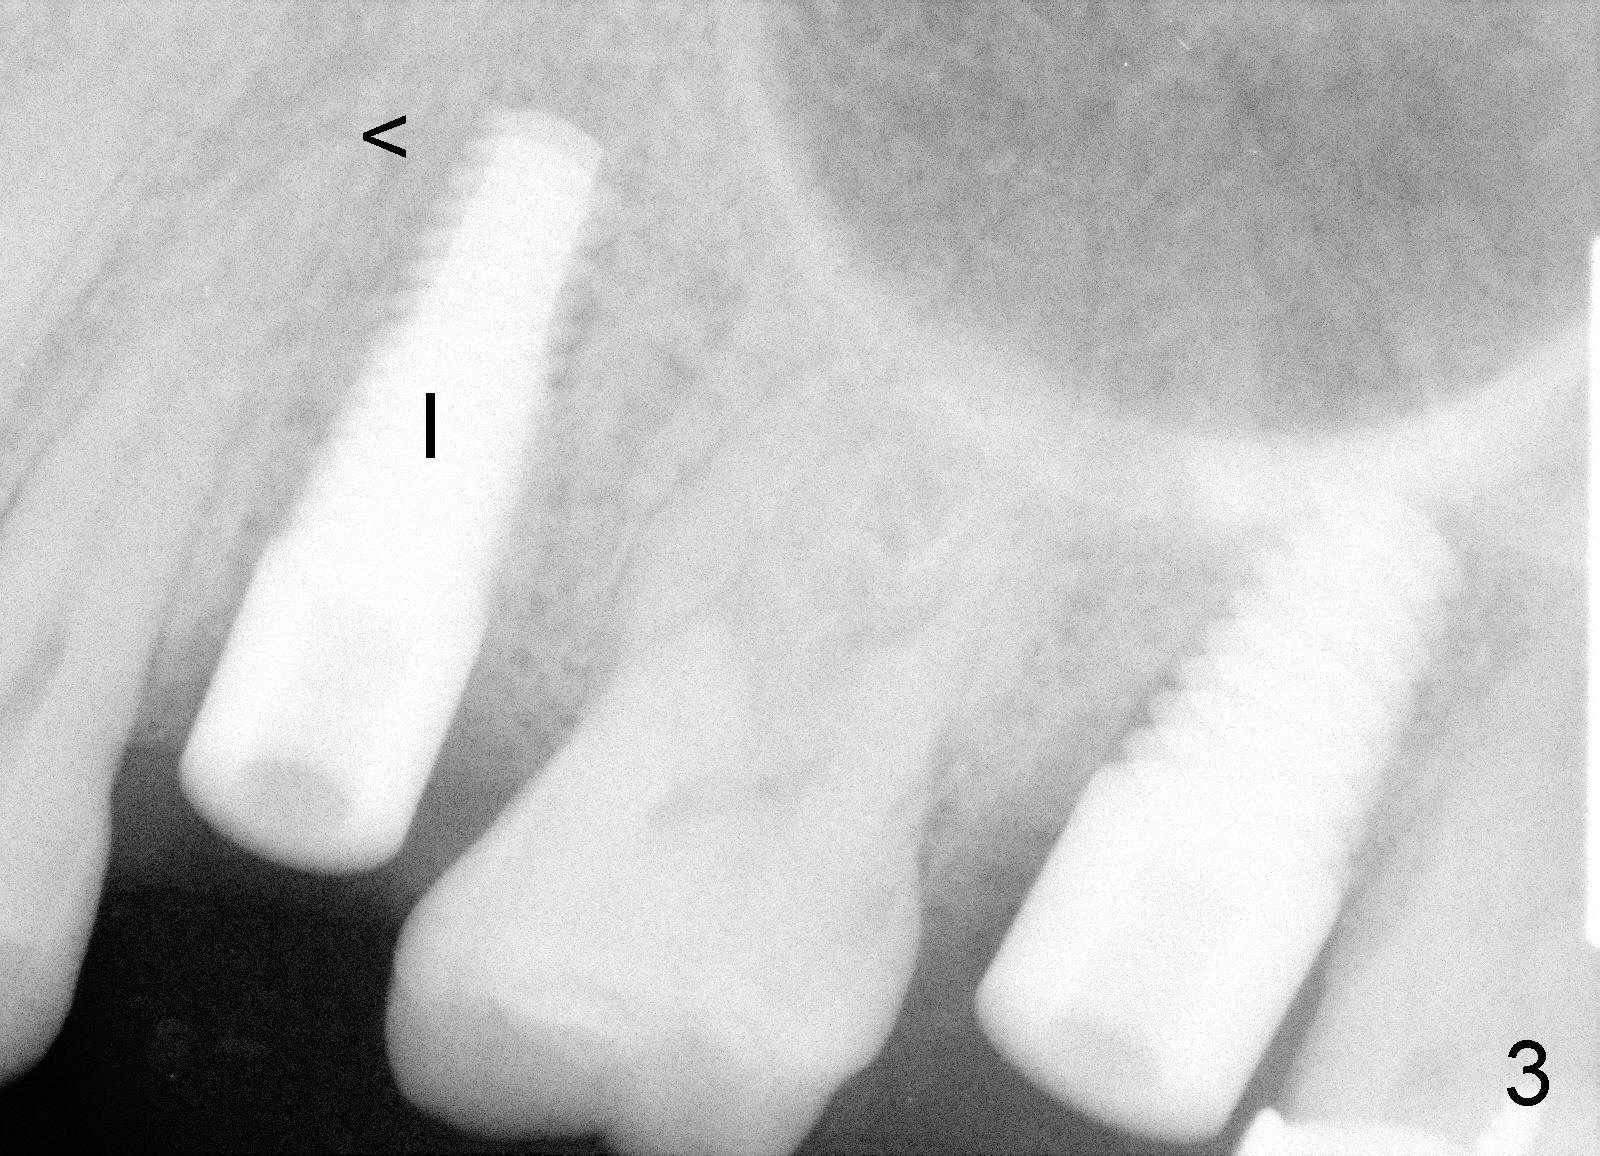

牙根拔除后,牙槽窝深度十六毫米(从牙龈缘算起),开始钻洞十七毫米深,一直用到钻头直径四点五毫米,然后用适当力量旋入五乘十七毫米tap(图二),后者与牙槽窝接触很紧,突然意识到即刻植牙后,牙龈会有所退缩,所以钻洞再深一毫米,最后旋入五乘十七毫米植牙(图三I),torque超过六十Ncm。原先第一双尖牙(图一黄线)比第二长些,术后植牙稍微比第一双尖牙长(图三箭头),总之在新骨头里钻洞不需要太多,在这个病例里,大约二个毫米。